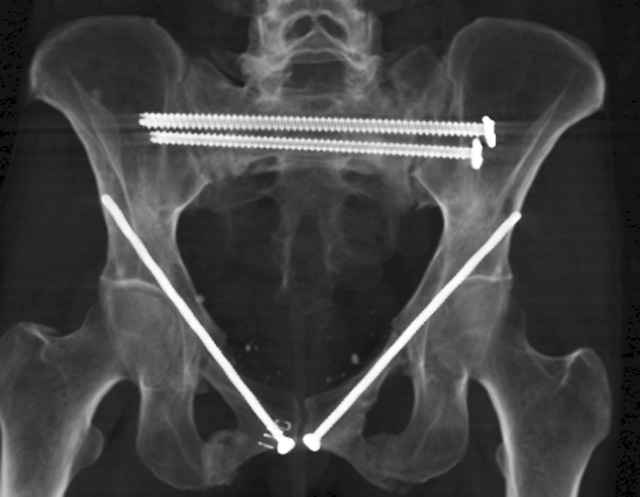

Here are a recent patient’s example slides...

Percutaneous Fixation

(B) Ramus-Retrograde

2 TransIliac-TransSacral

Upper Segment

mlcr